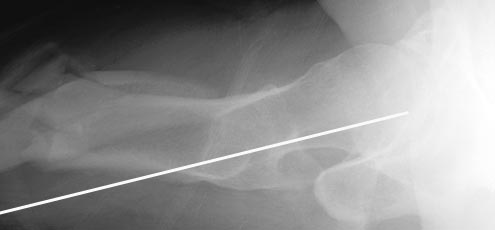

Отправитель: Alexander Chelnokov 11 Ноябрь 2010, 17:59

АЖ> Дык и я о том же! Не о репозиции перелома, а о введении штифта в

При многооскольчатых переломах стержень может "выпасть" кзади под весом кондуктора и своим, даже если поначалу он вводился правильно. Чтобы эту неприятность предупредить, стоит ввести спицу по оси шейки бедра вдоль ее задней стенки, типа как на картинке. Если стержень кпереди от этой спицы вводить, то он за нее не провалится.